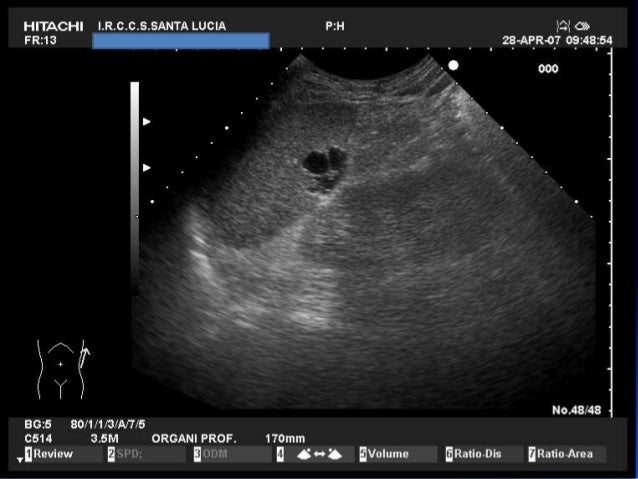

La milza ha la forma di un ovoide appiattito, con il maggior asse orientato obliquamente, dall’alto in basso, da dietro in avanti e dall’interno all’esterno;. La milza è un organo interno, delle dimensioni di un pugno, che si trova nell'addome umano Le funzioni della milza come parte del sistema immunitario e contribuisce alla produzione e stoccaggio di globuli come parte del sistema circolatorio Anche se la milza è un organo importante, ma non è essenziale per la sopravvivenza umana. Ecografia dell'addome superiore tecnica di misurazione delle dimensioni della milza normale, nel caso in esame.

Le dimensioni di una milza normale e sana possono variare considerevolmente da persona a persona Anche il tuo sesso e la tua altezza possono influenzare le sue dimensioni In generale, una milza adulta è lunga circa 5 pollici, larga 3 pollici, spessa 1,5 pollici e pesa circa 6 once. Ecografia dell'addome superiore tecnica di misurazione delle dimensioni della milza normale, nel caso in esame. Oltre alle dimensioni della milza, altri parametri devono essere presi in considerazione per la valutazione dei rischi connessi alla procedura Infatti, il tipo di patologia ematologica può giocare un ruolo fondamentale Inoltre, altri parametri relativi allo spazio di lavoro addominale sono da considerare, come l'habitus corporeo, l'indice di.

Fra le più importanti si ricordano quella emocateretica (distruzione dei globuli rossi non funzionali o deteriorati), quella immunologica, quella emopoietica e quella di separazione delle cellule ematiche e del plasma. Ecografia dell'addome superiore tecnica di misurazione delle dimensioni della milza normale, nel caso in esame. Pesa da 180 a 250 g ma questo valore, insieme alle dimensioni, varia in funzione della quantità di sangue che l.